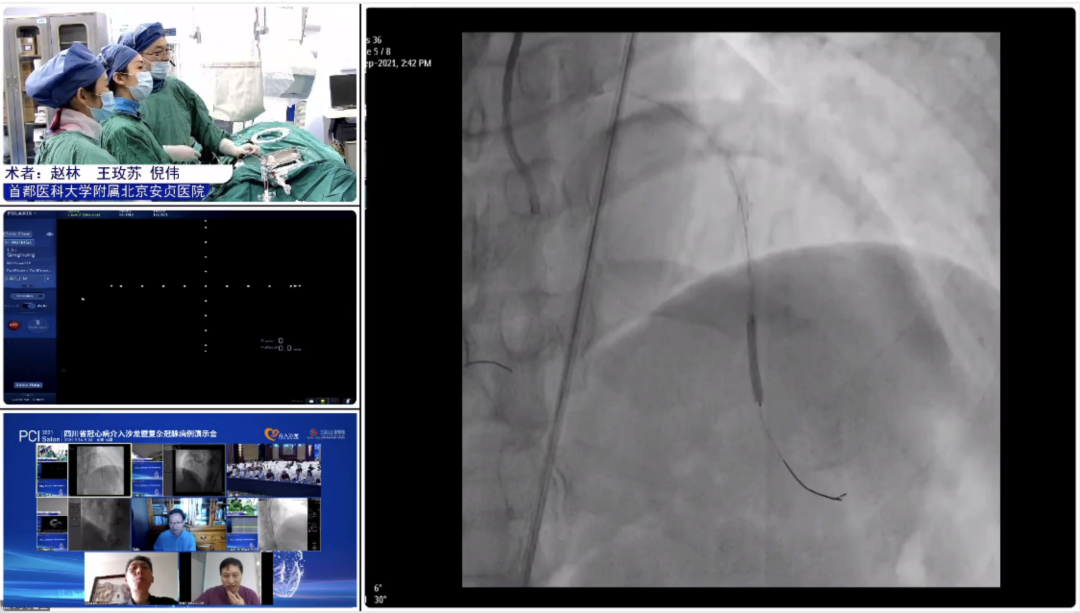

9月25日,大会隆重开幕,大会执行主席、四川大学华西医院贺勇教授主持,大会创始人及名誉主席、四川大学华西医院心内科黄德嘉教授,北京力生心血管健康基金会管廷瑞理事长,大会主席、四川大学华西医院陈茂教授,大会创始人及名誉主席东莞康华医院贾国良教授等多位专家领导分别以线上、线下参会形式共同出席开幕式,并为大会开幕致辞。随后,来自全国多地的冠脉领域资深术者通力配合,带来了11场极具难度和技巧的复杂冠脉病例手术演示及微课讲座。同期进行的护理及技术人员论坛、冠脉腔内影像与生理学论坛、冠心病诊疗论坛、降脂治疗论坛&心衰药物进展论坛、血栓抽吸、药物球囊、愈合型支架等专题学术内容应接不暇、精彩纷呈。